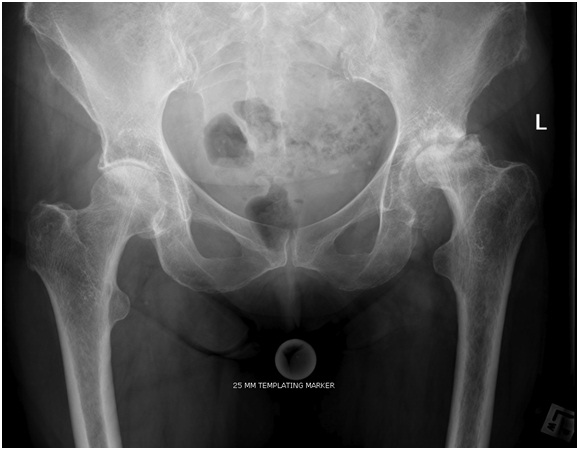

Around the hip joint there is the bone of the joint, the lining cartilage and labrum, the joint lining and capsule as well as muscles and other tissue which surround the hip. In young people pain is often associated with injury or inflammation from overuse. Sometime there may be an abnormally shaped hip or hip socket (acetabulum) which can lead to hip pain. In Elderly people hip pain is more commonly caused by arthritis. Occasionally the bone in the hip can die in a condition called Avascular necrosis.